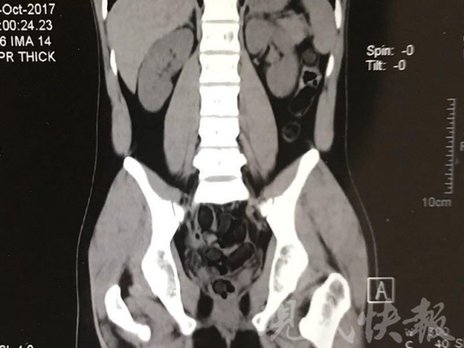

由于毒品在體內(nèi)一旦泄露有可能致命,警方第一時間將阿永帶到醫(yī)院進(jìn)行檢查。CT 掃描的結(jié)果顯示,阿永體內(nèi)布滿了密密麻麻的白色圓柱狀固體,就像一粒粒的蠶蛹。在南京市公安局鼓樓分局二板橋派出所,阿永分四次排出了毒品,毛重369.99克。經(jīng)訊問,阿永交代了自己全部的犯罪事實(shí)。目前,阿永已被刑事拘留。